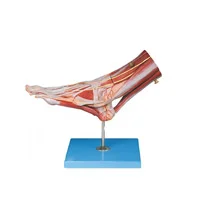

مولاژهای آناتومیک:

- مولاژهای کامل بدن: مدلهایی که تمام بخشهای بدن انسان را به طور کامل و تفصیلی نمایش میدهند.

- مولاژهای اعضای خاص: مدلهایی که بر روی اعضای خاص بدن مانند قلب، کبد، ریهها یا کلیهها تمرکز دارند.

مولاژهای آناتومیکی: این دسته شامل مدلهای بدن کامل یا بخشهای خاص مانند قلب، ریهها، سیستم گوارش و غیره است. این مولاژها به درک بهتر ساختار و عملکرد اعضای بدن کمک میکنند.

ماکتهای آناتومیکی: این ماکتها نمایانگر ساختارهای مختلف بدن انسان از جمله اسکلت، عضلات، سیستم عصبی و سیستمهای داخلی هستند. این ماکتها ممکن است به صورت کامل یا بخشهای خاصی از بدن مانند قلب، ریهها و کبد طراحی شوند.

- ماکتهای آناتومیکی: برای نمایش جزئیات آناتومی بدن، از جمله اسکلت، عضلات، و اعضای داخلی.

۱. مولاژهای آناتومیکی

این مولاژها برای مطالعه و درک ساختارهای مختلف بدن انسان طراحی شدهاند. شامل موارد زیر هستند:

- مولاژهای استخوانی: شبیهسازی دقیق اسکلت انسان، مناسب برای آموزش آناتومی استخوانها.

- مولاژهای عضلانی: نمایش عضلات اصلی و گروههای عضلانی بدن.

- مولاژهای سیستمهای داخلی: مانند سیستم گردش خون، تنفسی و گوارشی، برای مطالعه و آموزش عملکرد این سیستمها.